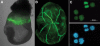

Erythroid (red blood) cells are the first cell type to be specified in the postimplantation mammalian embryo and serve highly specialized, essential functions throughout gestation and postnatal life. The existence of 2 developmentally and morphologically distinct erythroid lineages, primitive (embryonic) and definitive (adult), was described for the mammalian embryo more than a century ago. Cells of the primitive erythroid lineage support the transition from rapidly growing embryo to fetus, whereas definitive erythrocytes function during the transition from fetal life to birth and continue to be crucial for a variety of normal physiologic processes. Over the past few years, it has become apparent that the ontogeny and maturation of these lineages are more complex than previously appreciated. In this review, we highlight some common and distinguishing features of the red blood cell lineages and summarize advances in our understanding of how these cells develop and differentiate throughout mammalian ontogeny.